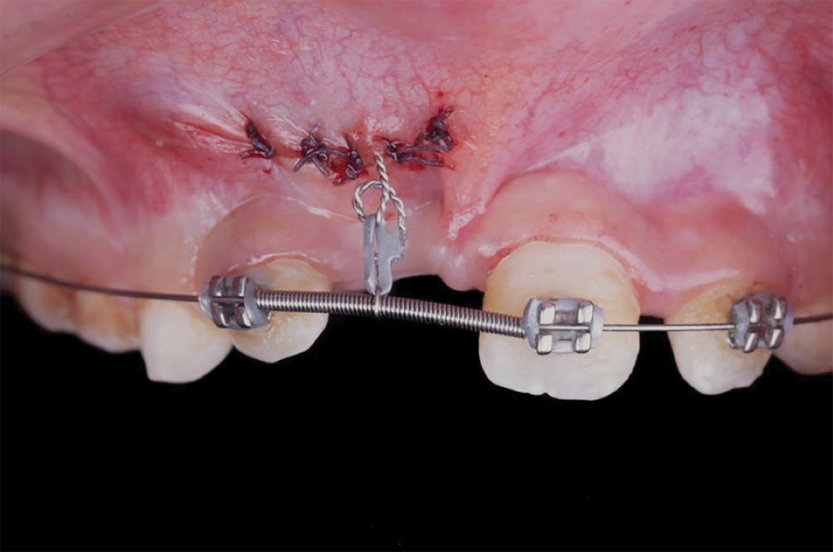

Fig 12. After expansion of the maxillary arch, the modified palatal expander was used for traction of the impacted maxillary right central incisor. Fig 12: Palatal expansion to gain space in the premaxilla for the impacted maxillary right central incisor. Fig 13: Traction of the impacted maxillary right central incisor through a palatal orthodontic attachment and the use of a power arm incorporated in the expander. Fig 14: Detailing the position of the impacted maxillary right central incisor with orthodontic fixed appliances.

Figure 12

Fig 13. After expansion of the maxillary arch, the modified palatal expander was used for traction of the impacted maxillary right central incisor. Fig 12: Palatal expansion to gain space in the premaxilla for the impacted maxillary right central incisor. Fig 13: Traction of the impacted maxillary right central incisor through a palatal orthodontic attachment and the use of a power arm incorporated in the expander. Fig 14: Detailing the position of the impacted maxillary right central incisor with orthodontic fixed appliances.

Figure 13

Fig 14. After expansion of the maxillary arch, the modified palatal expander was used for traction of the impacted maxillary right central incisor. Fig 12: Palatal expansion to gain space in the premaxilla for the impacted maxillary right central incisor. Fig 13: Traction of the impacted maxillary right central incisor through a palatal orthodontic attachment and the use of a power arm incorporated in the expander. Fig 14: Detailing the position of the impacted maxillary right central incisor with orthodontic fixed appliances.

Figure 14